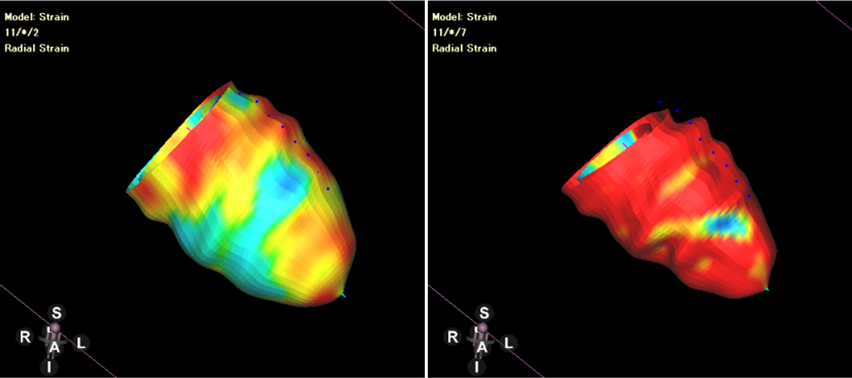

(1)strain(Figs. 11–13, Movies 2–5)

Fig. 13 Left ventricular radial strains in 3D view

strainは元来エコーで発展した指標で,CMRでstrainを計測するには,以前は心筋組織にtagを付けて撮影するtaggingという撮影を追加で行う必要があり,手間や時間がかかった.しかし,(撮影機器と)解析アプリケーションの発展に伴い,ルーチンで撮影するシネMRI画像から,feature trackingという方法を用いて後方視的にstrainが計測できるようになった21).feature tracking法はMRIの磁場などとは関係ない,ピュアな画像処理技術に基づいている.不規則性も含めたその画像上の心筋の特徴をとらえることで,細かく分けた心筋1箇所1箇所が心収縮期の中でどのように移動(収縮・拡張)するかを追跡することが可能になったのである.移動速度を計測することでstrainが算出される.feature tracking法という技術革新により,前方視的な研究だけでなく,過去に撮影した症例のシネMRIからstrainを振り返って解析できるようになることも特徴である.時間分解能(1心拍をエコーは60フレーム以上程度,CMRは20~30フレーム程度で撮影)や空間分解能(画像のslice厚)においてCMRはエコーに劣るが,これまで臨床的な意義がはっきりしていなかったstrainの様々なエビデンスがfeature tracking法により集まってきており,今後のさらなる発展が期待される.なお,解像度が悪く,追加撮影も要するtagging撮影は行われなくなった.

strainの解析結果・方法

左室全体としての心筋ストレインをglobal strainといい,それぞれの方向でglobal circumferential strain(GCS),global radial strain(GRS),global longitudinal strain(GLS)と呼ばれる.四空長軸像や左室二腔像,短軸像などの断面像を用いて以下の方法に則って心室strainの解析を行うと,GCS,GRS,GLSがそれぞれ算出される.また,これらの断面を複数組み合わせて同時に解析を行うことで3Dでのstrain解析を行うことが可能となり,AHA 16 segment modelでの結果表示や,心室3Dモデルにカラーを載せて結果を表示することも可能となる.一例として,解析アプリケーション“CVI42”(Circle Cardiovascular Imaging, Calgary, Canada)を用いた解析結果を示す(Figs. 12, 13, Movies 2–5).